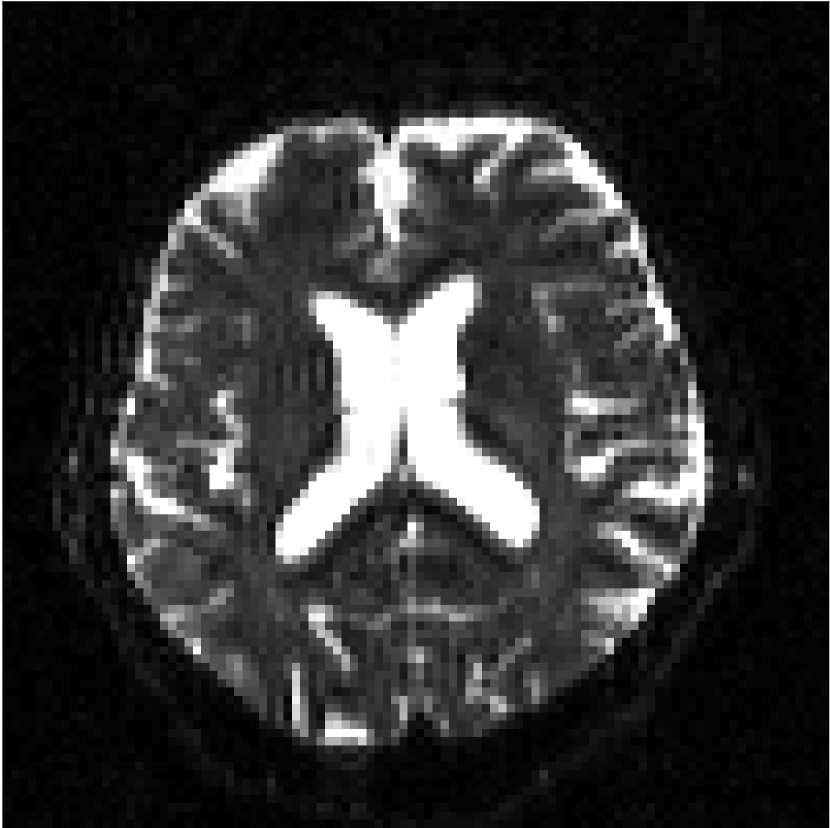

Figure 8 shows examples of non-diffusion-weighted images before and after processing. The raw images (Raw) served as the input for the magnitude deep learning (MCNN) and complex deep learning (CCNN) methods.

Raw

MCNN,

MCNN Resid.,

CCNN,

CCNN Resid.,

No PF

5/8 PF

Both methods remove artifacts, but the MCNN method allows residual rippling artifacts to pass through in the presence of partial Fourier. These rippling artifacts are not present in the CCNN method.